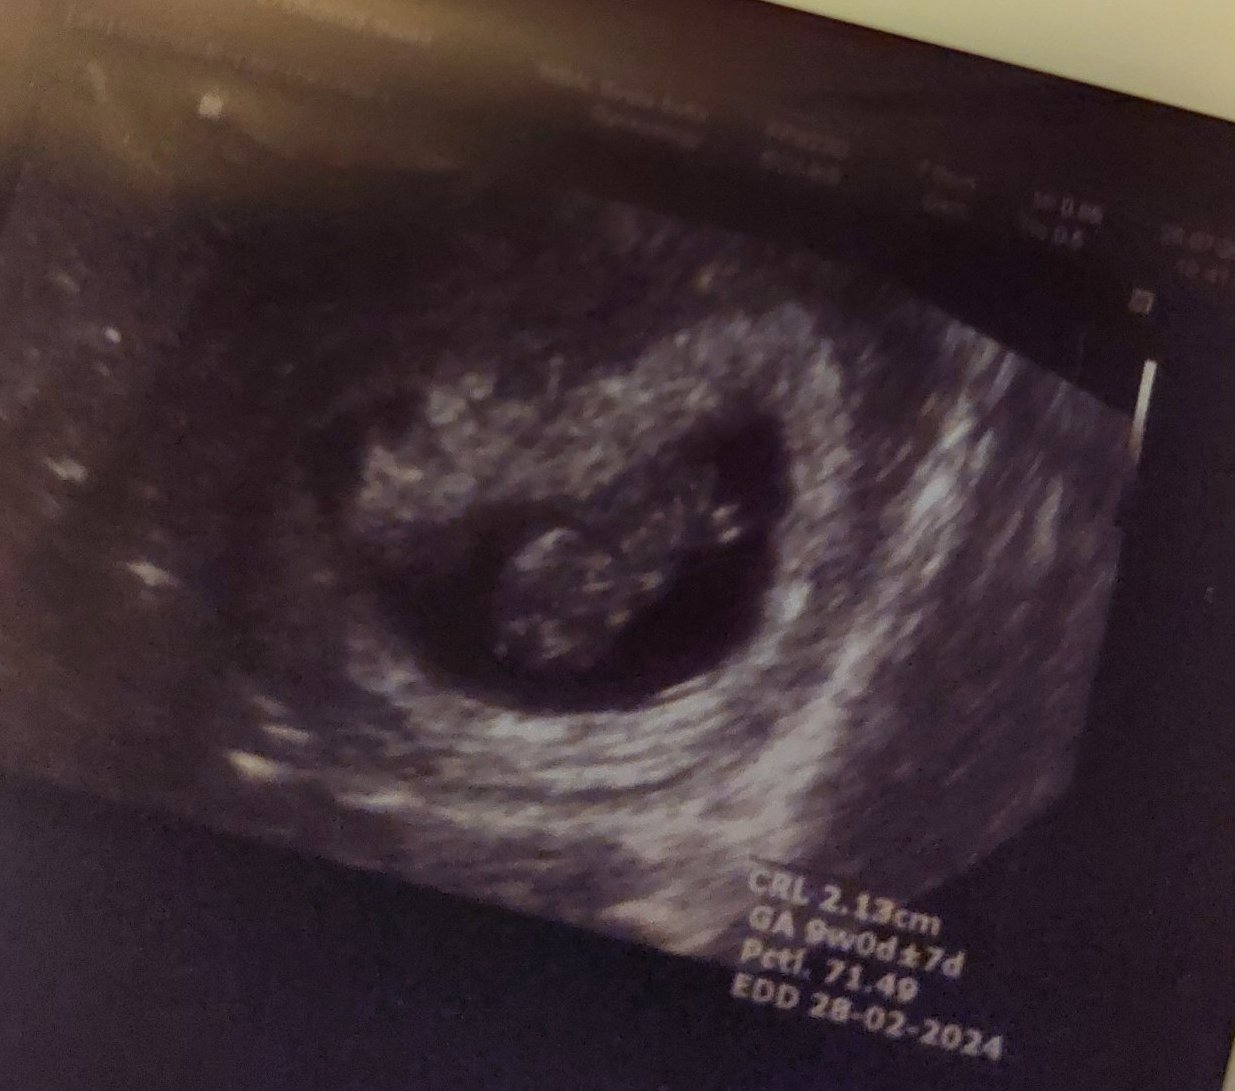

Здравейте! Идвам да споделя щастието си, че днес чухме пулс с ММ. ♡♡♡

Бях при д-р Лекова в Св. София. Прекрасна е! Толкова мила и обясни всичко на мен и мъжа ми изключително подробно и разбираемо. Изчислихме термин за 2 март, но каза, че вижда бебето с 4 дни по-голямо, та може и февруарско мами да съм.❤️ Щастието е неописуемо! Признавам си, че се разплаках като чухме пулс. Пожелавам го на всички тук! Неповторимо усещане..

Прегледът струваше 110лв. Беше много обстоен. Пита ме за оплаквания, какви витамини пия.. след това ми погледна един куп изследвания - пкк, урина, витамини, хормони, тромбофилия. И коментира всичко, което видяхме. Обясни ми подробно кое какво защо.